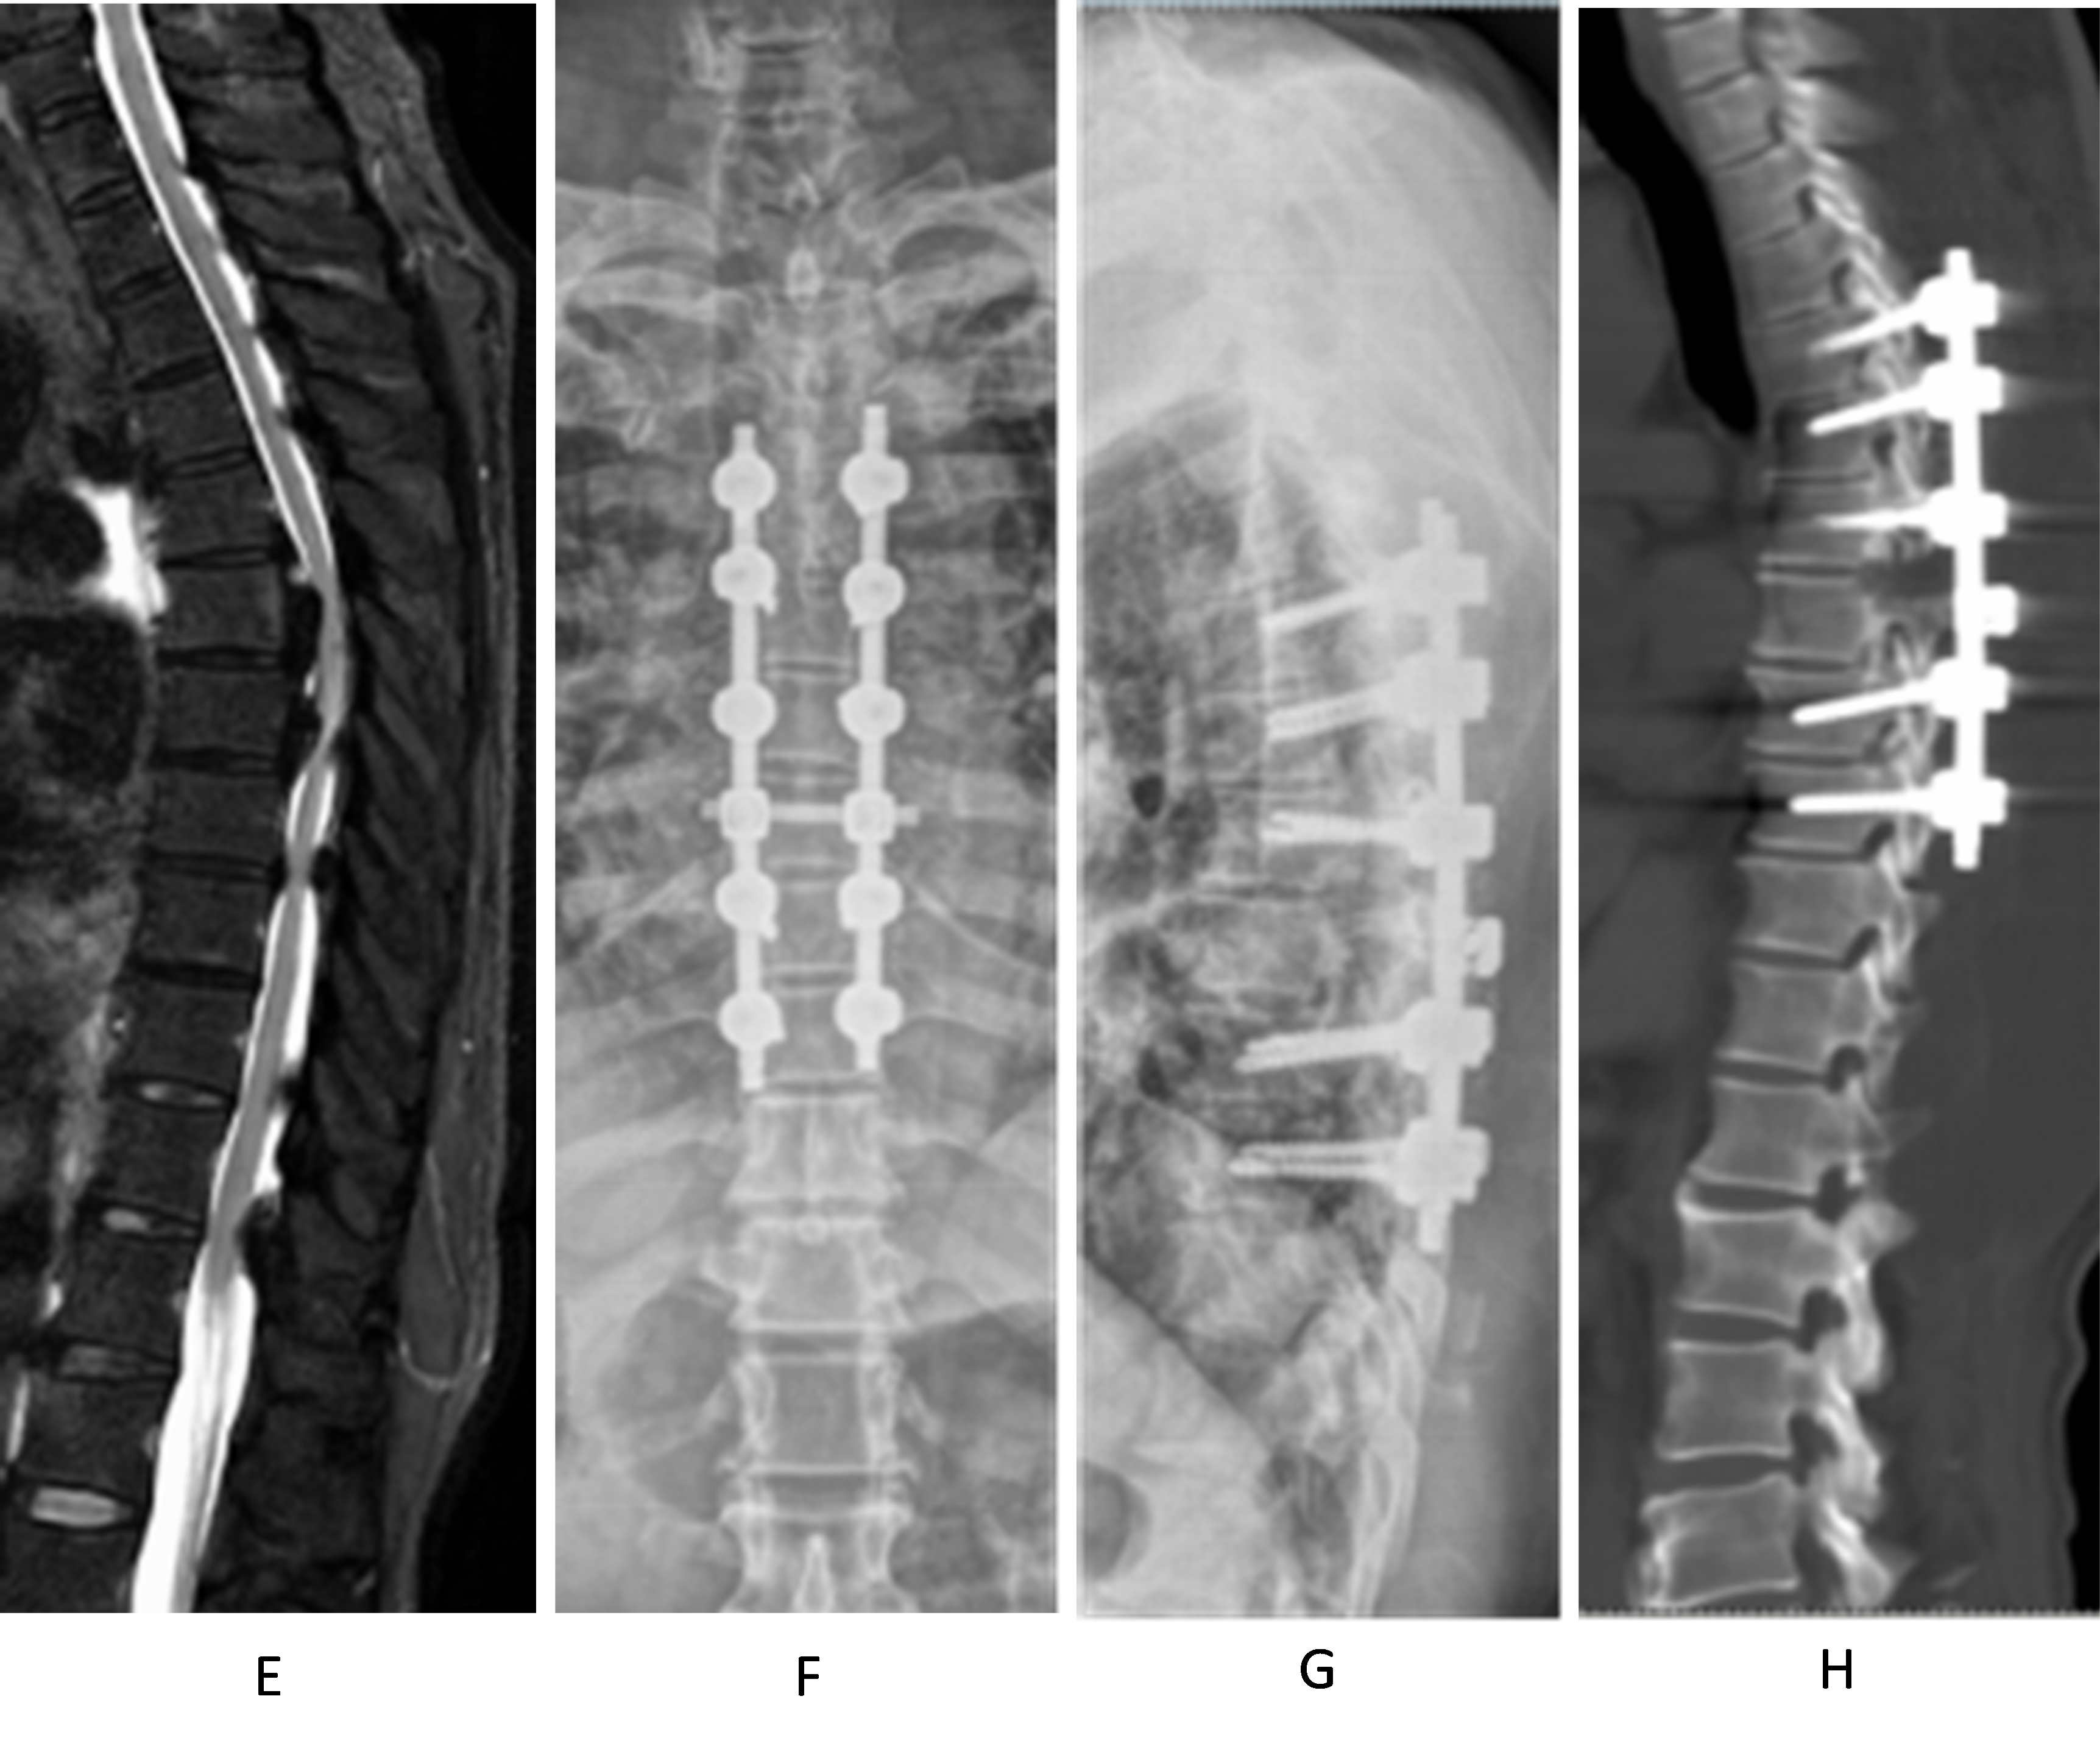

Figure 3 (E–H). E shows the preoperative thoracic MRI: Ossification of the posterior longitudinal ligament (PLL) of T5–7 and ossification of the ligamentum flavum of T4–7 can be seen together with anterior and posterior compression of the segmental spinal cord. F and G show the postoperative thoracic X-ray: T3–8 pedicle pins were well positioned; H shows the postoperative thoracic CT sagittal view: T4–7 laminectomy was performed, and T5–6 PLL ossification was cut off to de-convex the kyphosis. Both facet joints were partially removed. The preoperative and postoperative Cobb's angles were 30° and 15°, respectively.

Figure 3 (I–L). I shows the postoperative thoracic spine CT sagittal view, demonstrating laminectomy of T4–7, resection of the ossified posterior longitudinal ligament (OPLL) at T5–6, and correction of kyphosis with a Cobb angle of 15° in the stenotic segment; J Comparison of preoperative (upper) and postoperative (lower) thoracic spine CT transverse views. Upper figure shows the OPLL within the spinal canal; lower figure shows the resection of the OPLL and circumferential decompression. K and L show the three-dimensional reconstruction images of thoracic spine CT at the final follow-up, demonstrating posterolateral spinal fusion and the condition within the spinal canal.